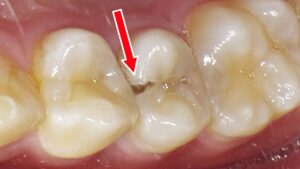

下顎6番の重度虫歯 ― 口腔内所見とレントゲンから抜歯に至った症例

下顎6番(第一大臼歯)に大きな欠損が認められ、口腔内写真では歯質が大きく崩壊している状態が確認できます。レントゲン画像では、虫歯が歯冠部から歯根深部まで進行し、歯根周囲の骨吸収および根尖部の透過像が明瞭に認められました。保存治療による改善が困難と判断され、感染源の除去と周囲組織の回復を目的として抜歯が適応となった症例です。

歯科医院でしか分からない内部の状態

小さな穴の内部がどうなっているかは、肉眼だけでは判断できません。

歯科医院では、以下のような方法で詳しく確認します。

- レントゲン撮影📸

目に見えない虫歯の広がりを確認できます。 - 探針や特殊器具によるチェック🪥

歯の柔らかさや隙間を調べて内部の状態を把握。

これらによって、外からは分からない虫歯の実態が明らかになります。